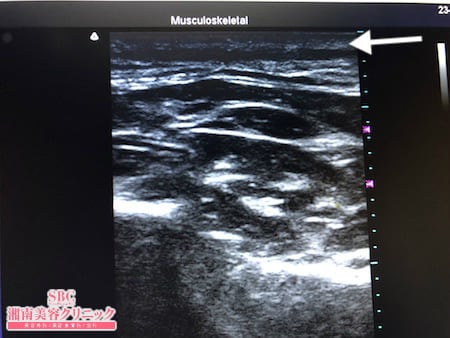

脂肪吸引に関する症例写真や動画はYouTube:sbctakeda-liposuctionで多数紹介していますのでぜひご覧になってください!https://www.youtube.com/watch?v=yv8lVb2ZqCIまたInstagram:nekosogitakedaTwitter:nekosogidoctorでも紹介していますのでぜひご覧になってください!今回紹介する患者様は現役のナースさんです。忙しく、かつ不規則な勤務体系のなかまた子育てに追われながら毎日を過ごし気がついたら随分と余分な皮下脂肪が全身に付いてしまいました。病院の制服も入らなくなるだけでなくお子さんからはお尻みたいなおなか!!と言われ今回患者様は脂肪吸引を決意されました。その術中変化を紹介しましょう。たくさんの皮下脂肪を可能な限り根こそぎ!!ましたので患者様には間違いなく大幅にボリュームダウンしたおなかを手に入れていただけると確信しています。この文章を書いている日は関西地方からも患者様にお越しいただいております。全国各地から患者様にお越しいただき本当に感謝しています。脂肪吸引をお考えの患者様はたとえ遠方からであっても根こそぎ竹田先生に会いにきてくださいね!!

その術中変化を紹介しましょう。